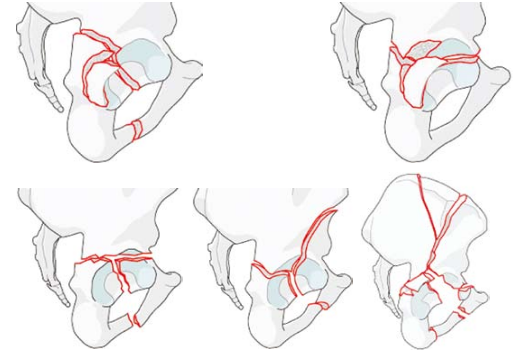

以下图片是我科骨盆髋臼骨折腹直肌外侧入路手术技术的两例患者资料。(骨二科)

实例一